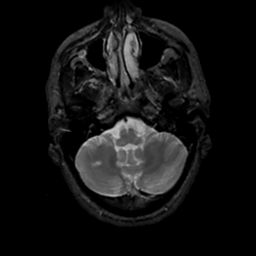

MR Study #7, March 24, 1991 -- Slice #9

[Home][Help][Clinical][Tour 1][Tour 2] Slice 9